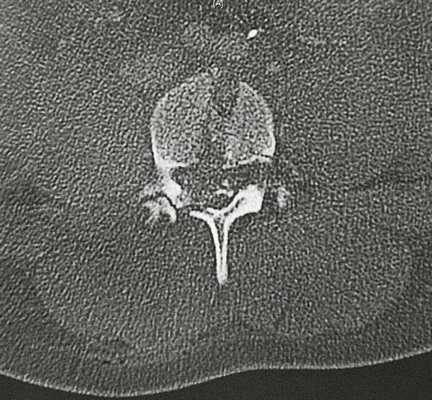

Компьютерная томограмма. Огнестрельные повреждения.

КТ сквозного огнестрельного повреждения головы оболочечной пулей.